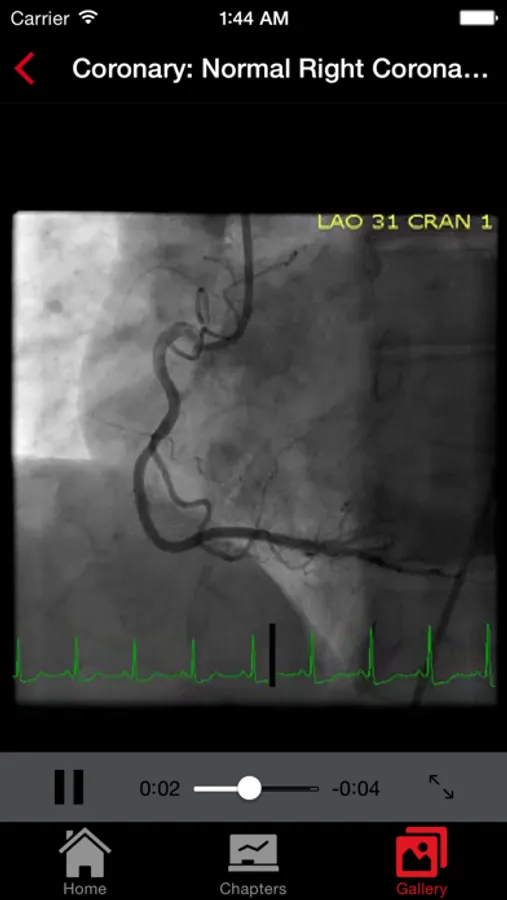

About CathSource

CathSource (from the creators of ECGsource) is an up-to-date medical reference devoted exclusively to cardiac catheterization and angiography. Developed by practicing Interventional Cardiologists for both specialists and trainees in the field of cardiovascular disease, CathSource offers the following content:

* Searchable database containing more than 30 videos (coronary angiograms, ventriculograms, and aortograms) of both common and rare findings in the cardiac catheterization lab

* Searchable database of over 65 images including hemodynamic formulas, tables, and figures

CathSource provides a detailed overview of important cardiac catheterization and angiography topics, incorporating educational images/videos as well as reviews of pertinent medical literature.

CathSource is the ideal application to assist you in understanding and recognizing cardiovascular pathology in the catheterization lab.

CathSource Screenshots